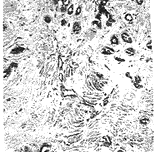

从上述时间表可以清楚地看出:将超声处理方法应用于快速切片中,可稳定地缩短组织处理时间,提高制片效率;同时根据质量观察,运用该方法制取的切片,组织收缩少,脆性小,切片薄而完整,染色特别鲜艳明丽,层次清晰,为提高镜检的准确性创造了条件;另外,组织蜡块和切片均能长期保存,不易褪色,有利于教学、科研和学术交流,完全符合优质病理切片的质量要求(见附图)。

结肠腺瘤性息肉 HE×40

脑星形胶质细胞瘤 HE×100

乳腺腺病 HE×100

乳腺浸润性癌 HE×100

附图 快速切片质量观察